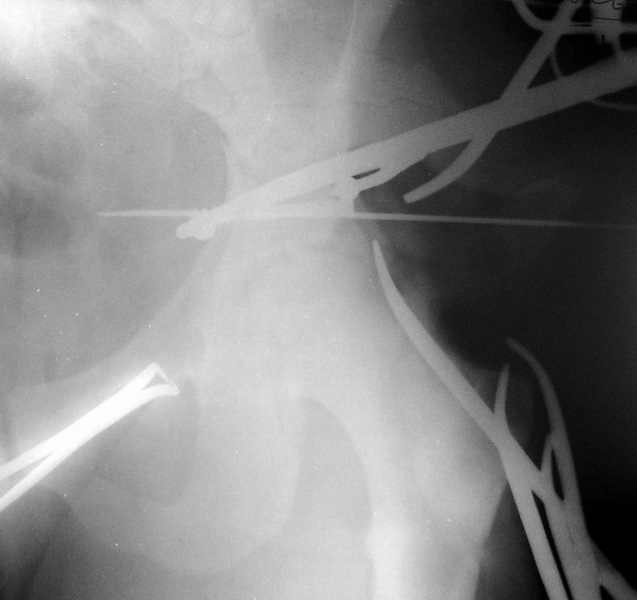

Есть такое дело. Хотя, похоже, зафиксировать здесь можно даже без специальных гвоздей для проксимального отдела. В приложении пример случая с подобным по величине центральным отломком.

Кликните для загрузки файла 1.jpg

19KB (19658 bytes)

Комментарии излишни - все ясно и без слов, качественная *сборка*.

Одним из альтернативных решений при подобном типе перелома - сверление доп. отверстия в гвозде, чтобы предовтратить излишнюю протрузию гвоздя из проксимального отломка.